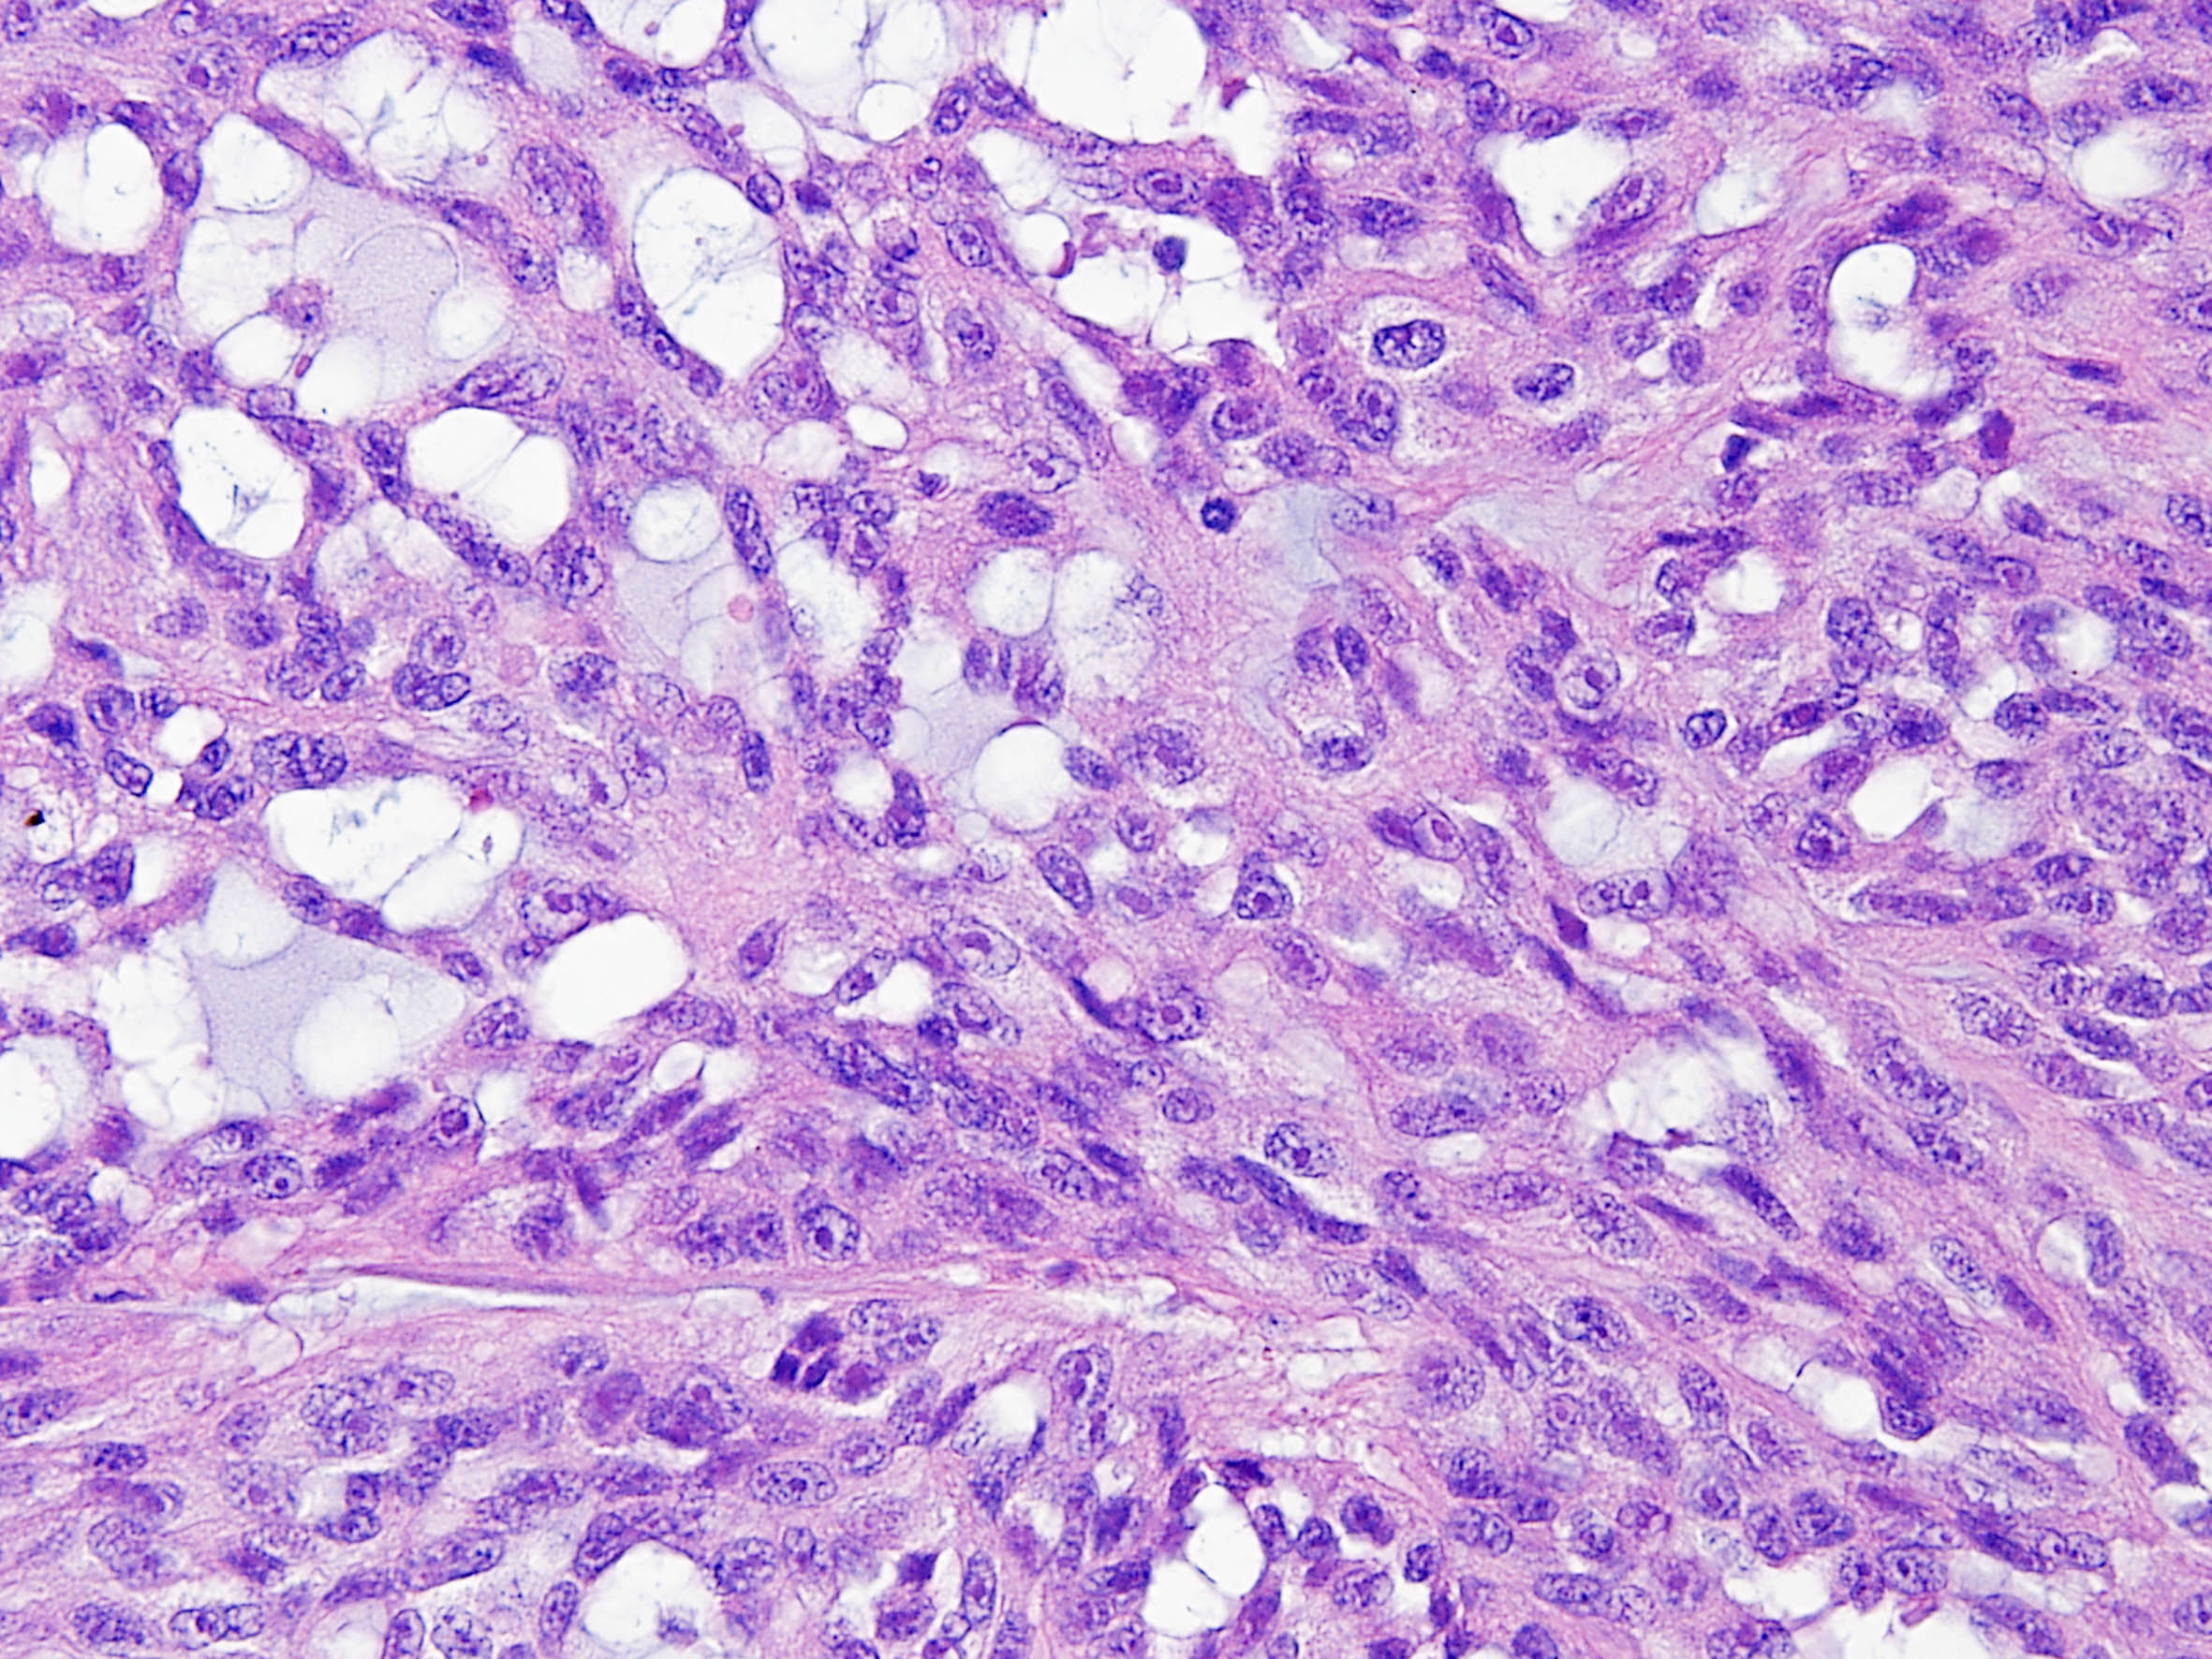

Classification of renal tumors

Case ID: 171